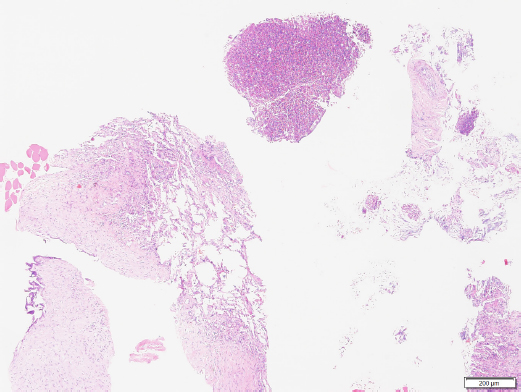

Histopathologic results of the sample confirmed marked, multifocal, chronic, neutrophilic, and eosinophilic granulomatosis with a fibrous capsule (Figs. 4 and 5).

Fig. 4. Histopathology of the pulmonary mass via a Trucut biopsy. Overview revealing fibrosis and an eosinophilic multifocal inflammatory component (40× magnification). Image courtesy of Dr. May TSE from CityU VDL, Hong Kong.